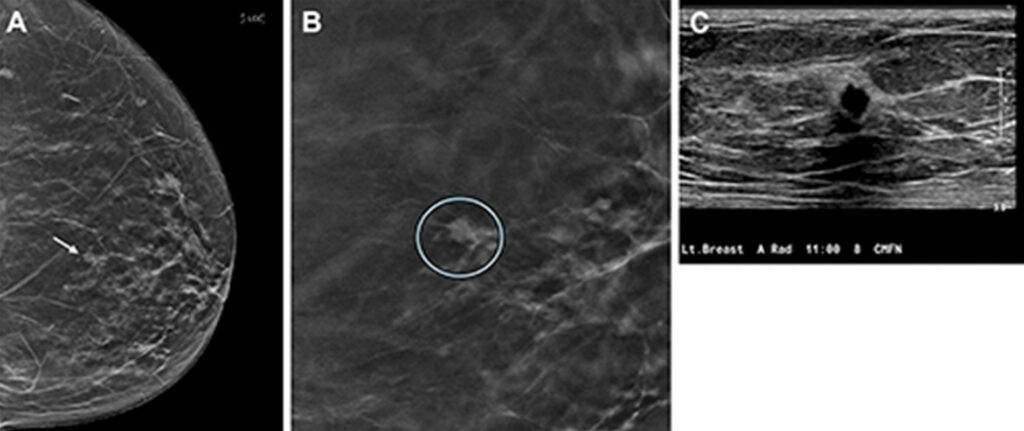

DBT is an advanced form of mammography that reconstructs pictures of the breast taken from different angles into 3D images. Studies have found that DBT has a higher cancer detection rate compared to digital mammography.

Most true-positive cancer cases detected by DBT presented as masses, while fewer presented as calcifications and asymmetries.